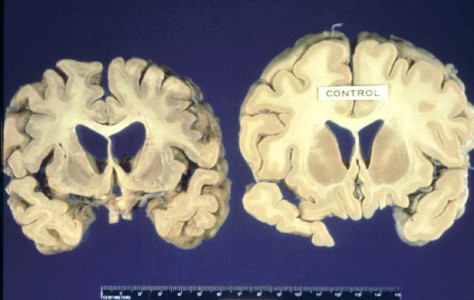

| 由SCP-609导致脑病的大脑和正常大脑对比 |

SCP-609所导致的脑病几乎和库鲁病完全相同,这种病是一种在巴布亚新几内亚的法尔人之中流行的疾病。导致库鲁病最初开始传播的因素是法尔人在葬礼上的食人性行为,这一疾病和他们吃掉尸体大脑有关,但这种疾病在一个人口中心出现还是引起了不小的震动。在受害者的脑中发现了朊病毒后,疾病中心才最终确定了病因。所有的受害者都有不久之前购买手机的经历(或者是,在两个病例之中,因为办公室的电话系统),并且在之前的一个半月之中收到了数百通电话。基金会特工最终发现了一群新雇用的音响工程师,他们之前一直在尝试改进手机铃声的音质。因为这工程师一开始在办公室临时工身上做实验,因此他们之中大部分都避免了被感染的命运。这些没有被感染的工程师马上被基金会所雇用,参加了[数据删除]实验。